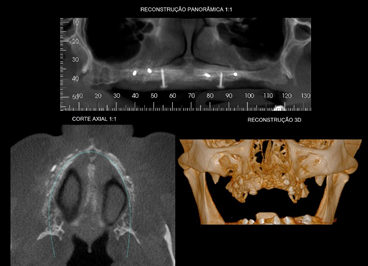

Paciente com edentulismo total maxilar foi indicado pelo profissional protesista para a instalação de implantes na região dos elementos ausentes: 11, 21, 22, 34, 35, 36, 45 e 36. Após exame clínico inicial e complementar com radiografia panorâmica e tomografia computadorizada de feixe cônico (TCFC), notou-se severa reabsorção óssea na maxila. No caso apresentado, a técnica de levantamento de seio maxilar não estava indicada, dado as características anatômicas dos seios maxilares hipoplásicos associadas à extensa reabsorção óssea de rebordo alveolar (Figuras 1 e 2).

Após o período de seis meses de cicatrização do enxerto, realizou-se a uma nova TCFC, onde foi possível constatar o ganho ósseo obtido (Figura 4).